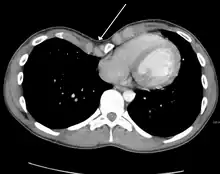

Masses

.jpg.webp)

Masses such as tumors can also cause compression and displacement of mediastinal structures. There are various mediastinal tumors and they are classified by their location in the chest. Notable examples include germ cell tumors and lymphomas.[12] Teratomas are a class of germ cell tumors that arise in the chest due to failure of germ cell migration during development. They can expand to large sizes and cause hemopytsis and pleural effusion. Radiographic features of teratomas typically include fluid and fat but also muscle, teeth, and bones inside the mass.[13]